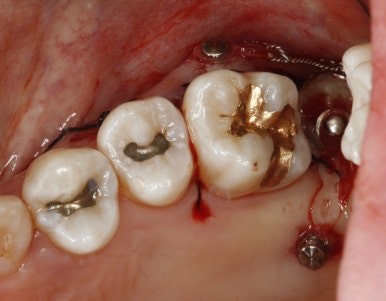

드디어 구강내로 얼굴을 내밀고 제 위치에 안착~